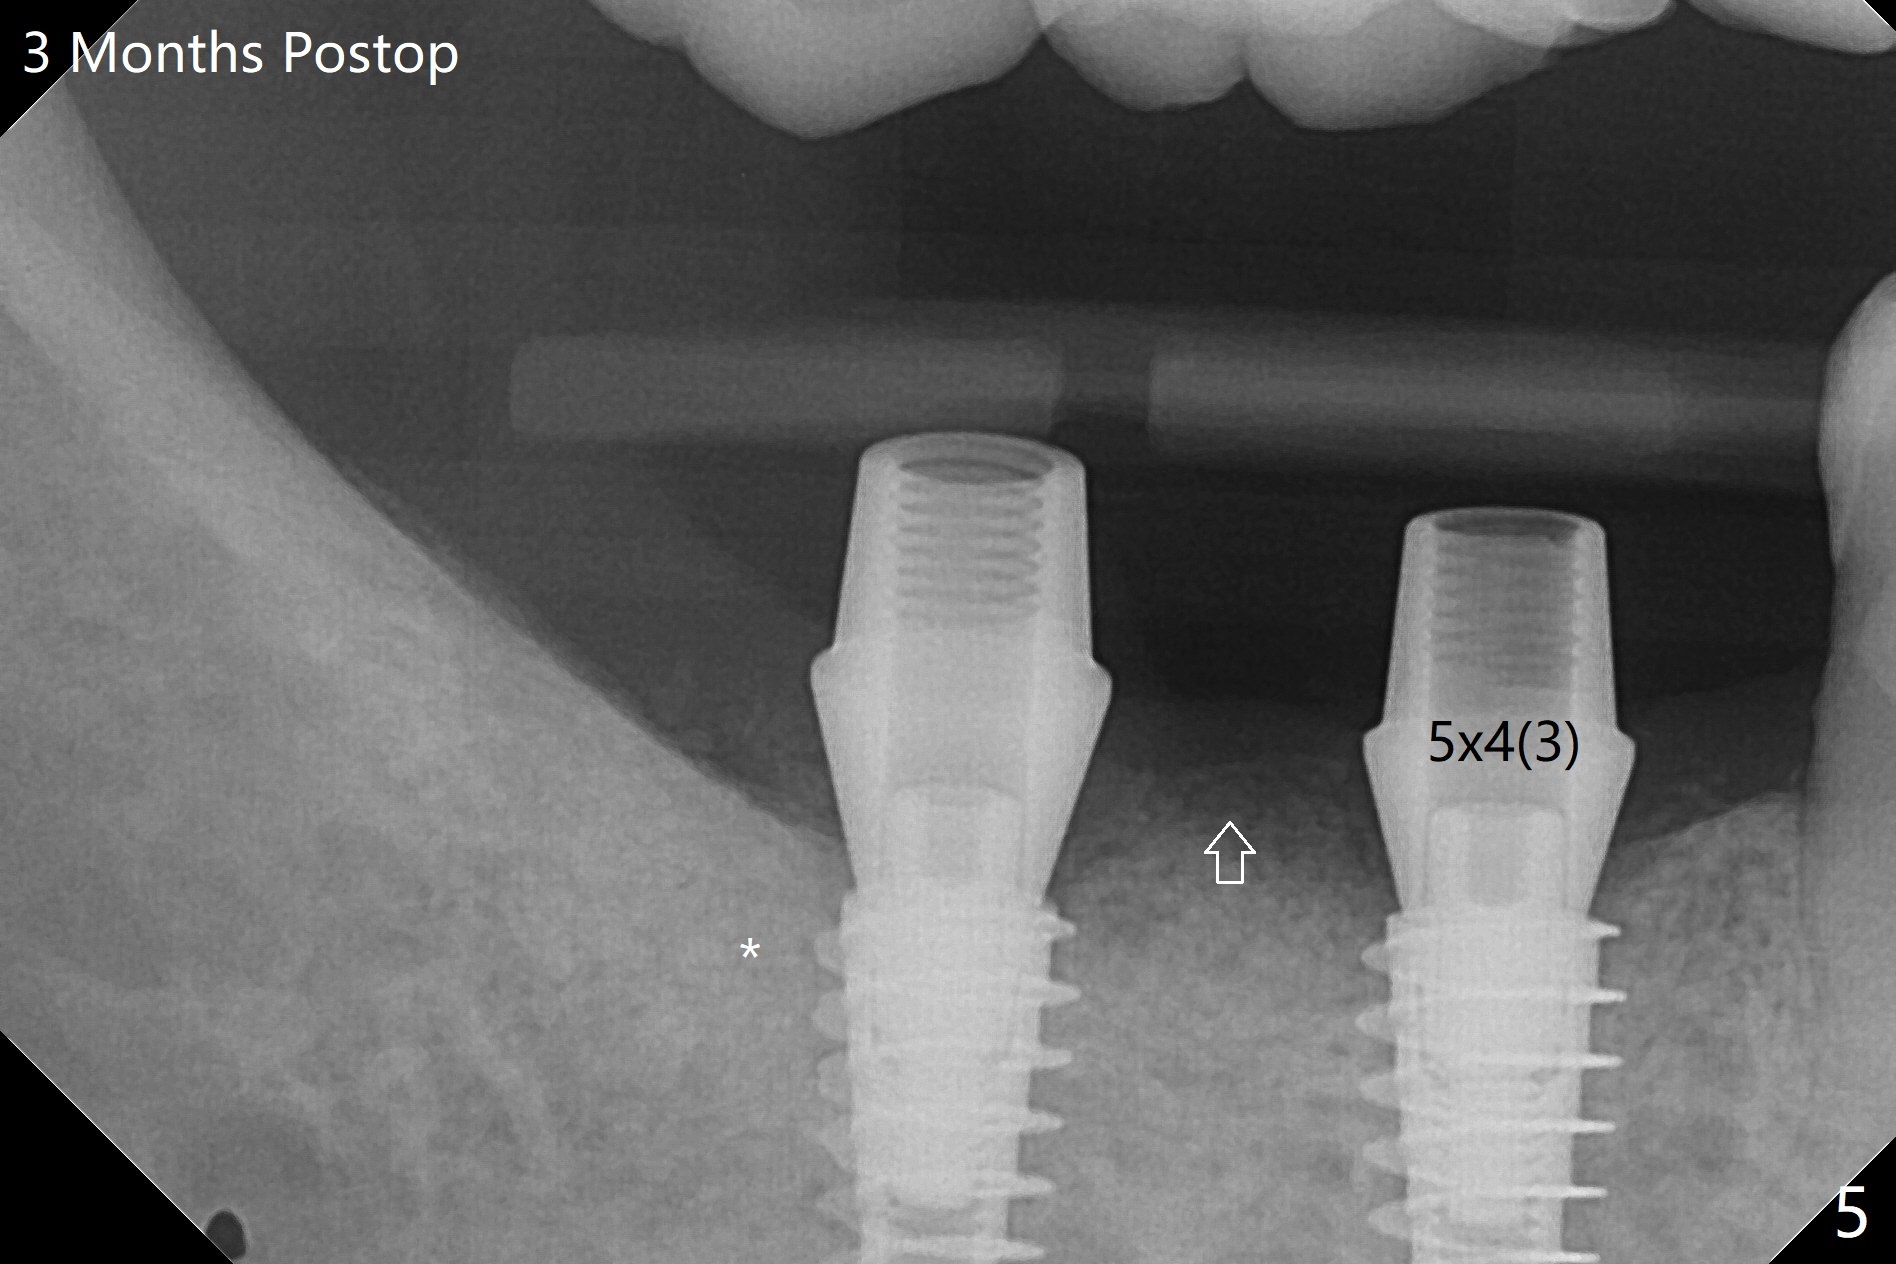

54岁男,右下6,7位点保留后7个月回来植牙,植牙床是个平面(图一),今后两个牙齿之间龈乳头一定缺乏,如何重建?放置导板,稍微使用环形钻头,在6,7植牙床上形成标记(图二),然后切开,植入植体,6扭力低,7高,所以安置愈合(6x5毫米)和修复(5.5x4(4)毫米)基台。原来导板设计把植体植入牙槽嵴(图三:白虚线)下1-2毫米,自动提高植体间牙槽嵴,接着把钻洞产生的骨粉放在后者上缘(*),由近中和远中基台固定。最后覆盖胶原膜,缝合(图四)。原来导板需要切除的角化龈保留住了(图四:7B,7L)。放入修复基台目的是利用它的高度固定牙周敷料。术后3个月7牙槽窝愈合(位点保存后10个月,图五:*),植体间牙槽嵴仍旧高(箭头),6放置修复基台,准备做临时牙冠。右上7反合,需要做局部矫正(图六)。病人非常感激术后三个月制作的临时牙冠(连体)。术后五个月对临时牙冠进行修改:6牙合面垫高(图七:*),这样上下7牙合面分开,上7颊侧放置矫正器,下7牙圈(舌侧有cleat),两者之间安置橡皮筋,上7就可以自由往舌侧移动。术后8.5个月全景片和CT显示植体种植牙槽嵴下(图八至十),这也是重建龈乳头基础。